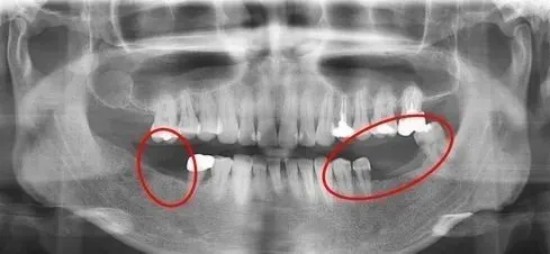

人類與其他生物在牙齒再生能力上存在天壤之別。鯊魚一生能夠不斷更換牙齒,而人類只有兩副牙齒:乳牙和恒牙。這種差異背后是數(shù)百萬(wàn)年的進(jìn)化選擇。乳牙通常在嬰兒6個(gè)月大時(shí)開始萌出,3歲左右長(zhǎng)齊。這套共20顆的牙齒較小且牙釉質(zhì)較薄,更容易蛀壞。恒牙則從6歲開始替換乳牙,這套28-32顆的牙齒需要陪伴我們一生。恒牙一旦脫落,就無(wú)法自然再生。這一進(jìn)化上的“設(shè)計(jì)缺陷”使得牙齒成為人體唯一不能自我修復(fù)的硬組織。也正因如此,全球有數(shù)以億計(jì)的人面臨缺牙問(wèn)題。

面對(duì)恒牙脫落,目前的主要解決方案是假牙或種植牙,但它們各有局限。種植牙雖然優(yōu)于傳統(tǒng)假牙,但仍無(wú)法完全替代天然牙的功能。

目前,牙齒缺失的主要修復(fù)方式包括活動(dòng)假牙、固定橋和種植牙,但它們各有優(yōu)缺點(diǎn)。種植牙雖然優(yōu)于傳統(tǒng)修復(fù)方式,但仍存在缺乏牙周膜的問(wèn)題。沒(méi)有牙周膜,種植牙無(wú)法感知食物的硬度,容易導(dǎo)致牙冠劈裂或種植體松動(dòng)。基于干細(xì)胞的牙再生技術(shù)將徹底改變這一局面,構(gòu)建了基于干細(xì)胞的成牙誘導(dǎo)新體系,創(chuàng)建了牙組織器官再生的功能模塊構(gòu)建新方法。這些突破使得“打針長(zhǎng)牙”的可能性越來(lái)越接近現(xiàn)實(shí)。